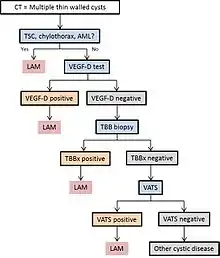

LAM can come to medical attention in several ways, most of which trigger a chest CT. Thin-walled cystic change in the lungs may be found incidentally on CT scans of the heart, chest or abdomen (on the cuts that include lung bases) obtained for other purposes. HRCTs of TSC patients reveals that about 20% of women have cystic change by age 20 and about 80% of women have cystic changes after age 40.[79] LAM is sometimes revealed by chest CT in patients who present with an apparent primary spontaneous pneumothorax, but more often CT scanning is not ordered (in the United States) until recurrences occur. Progressive dyspnea on exertion without the exacerbations and remissions that are characteristic of asthma or COPD sometimes prompt a chest CT. A review of the CT by an expert familiar with LAM may increase diagnostic accuracy.[80] Chylothorax can also bring LAM to attention.

In some cases, a LAM diagnosis can be made with confidence on clinical grounds (without biopsy) in patients with typical cystic changes on high resolution CT scanning of the lung and findings of tuberous sclerosis, angiomyolipoma, lymphangioleiomyoma, chylothorax or serum VEGF-D > 800 pg/ml.[70][81]

If none of these clinical features are present, a biopsy may be necessary to make the diagnosis. Video-assisted thoracoscopic lung biopsy is the most definitive technique, but transbronchial biopsy has a yield of over 50% and can also be effective.[82][83] The safety of the latter procedure in patients with diffuse cystic disease and the profusion of cystic change that predicts an informative biopsy are incompletely understood, however. Cytology of chylous fluids, aspirated abdominal nodes or lymphatic masses can also be diagnostic.[63][84][85][86]

Diagram 1 outlines a proposed algorithm for the diagnosis of LAM.